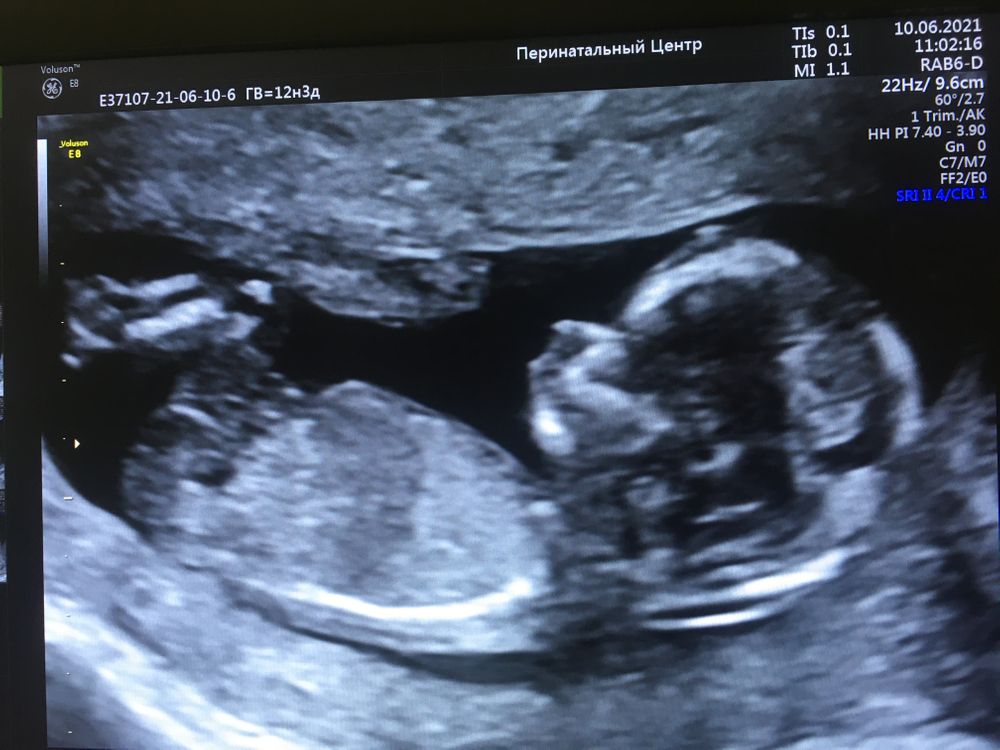

Скрининг первого триместра

Пупс это вам разрешили фото с экрана сделать ? у нас скрининг на следующей неделе чето так переживаю тоже

Апрельская, да. Фото с экрана ) Уже после исследовании вывели на экран для фото

На девочку очень похожа💝!

Toma Moon, половой бугорок идёт паралельно позвоночнику + строение черепа гладкое без сильной выпуклости в районе лба.

Toma Moon, ну если на фото половой бугорок виднеется, то он женский (длинненький такой светлыЙ).У девочки идет парралельно спинке, у мальчика чуть вверзх на 30градусов. И нужно смотреть еще вид снизу. У девочек щелочка будет ( 2 параллельных линии), а у мальчиков нет. Вид снизу есть, делали?